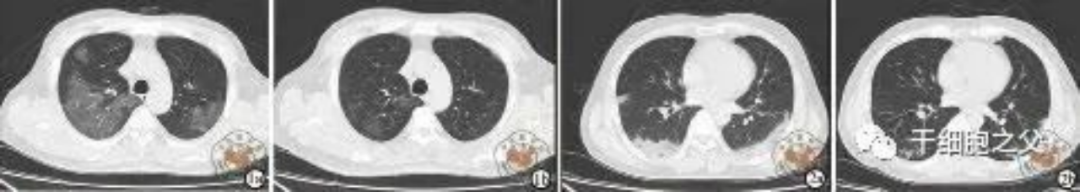

如圖所示,1a-1b:細(xì)胞輸注后,炎癥指標(biāo)改善,復(fù)查胸部CT提示雙肺病灶較前吸收,呼吸道癥狀改善,新型冠狀病毒核酸檢測連續(xù)2次陰性,治愈出院。圖2a-2b:2次干細(xì)胞輸注后炎癥指標(biāo)改善,復(fù)查時氧合指數(shù)升高至301 mmHg,胸部CT提示雙肺病灶較前吸收,患者呼吸道癥狀改善,新型冠狀病毒核酸檢測連續(xù)2次陰性,治愈出院。